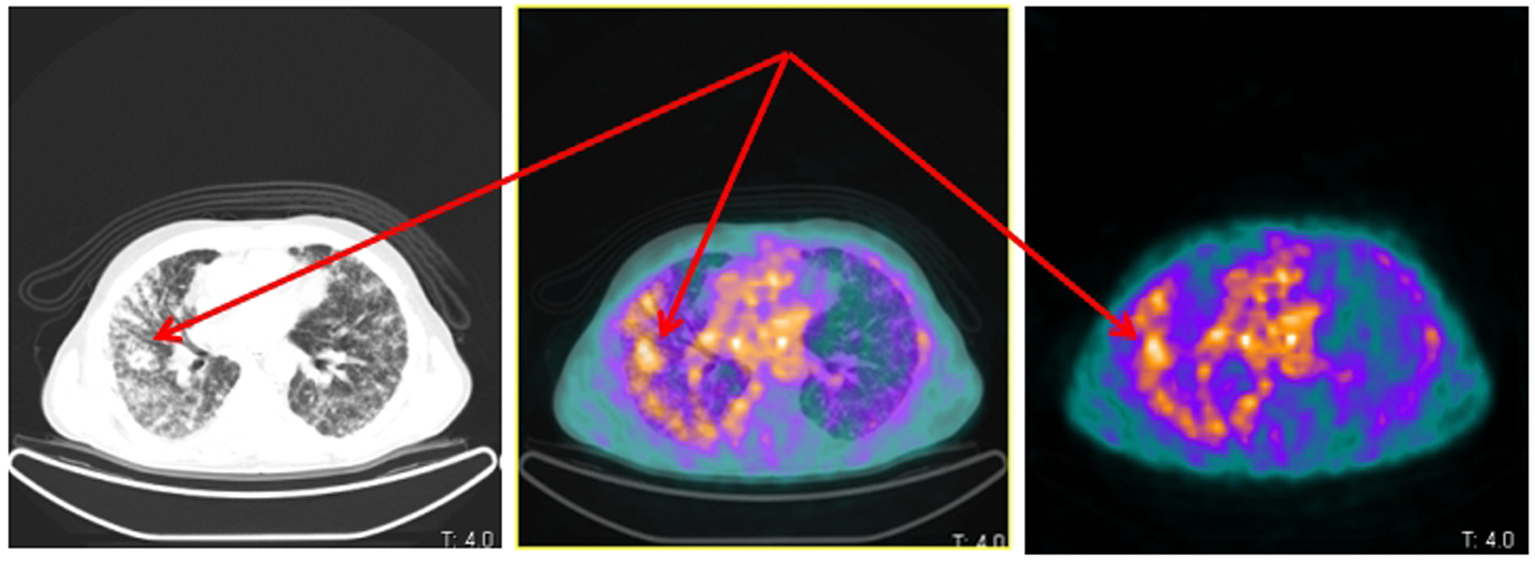

[68Ga-DOTA,1-Nal3]octreotide (68Ga-DOTANOC) PET/CT showed several areas of increased uptake located in bone metastases. The uptake was more significant in metastases with a lytic component on CT (Fig. 1). Moreover, two diffuse areas of increased lung uptake corresponding to lymphangitic neoplastic spreads were noted (Fig. 2). These finding were consistent for an NED of neoplastic cells with overexpression of SSTR2, SSTR3 and SSTR5.

![]() Click for large image | Figure 2. Same patient and acquisition parameters of Fig. 1. 68Ga-DOTANOC transaxial PET/CT (left CT attenuation correction, middle fused PET/CT, right PET only) showing increased uptake corresponding to lymphangitic carcinomatosis of the right lung (arrows). |